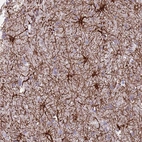

Immunohistochemical staining of human lymph node shows strong membranous positivity in non-germinal center cells.